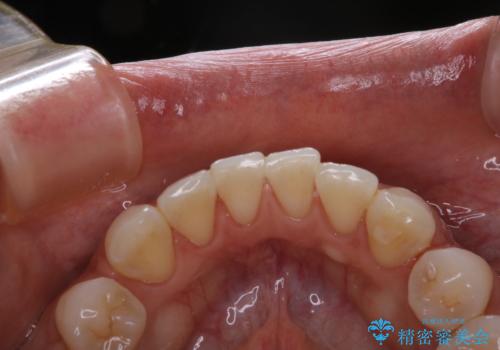

- フロスが以前よりも通りずらくなり、クリーニングしてほしいとのことでした。歯科医院でのクリーニングは3年ぶりとのことです。PMTC60分コースを行いました。

歯科医院で行なわれる専門家による徹底した歯面清掃をPMTC(Professional Mechanical Tooth Cleaning)といいます。専用の機器とフッ化物入り研磨剤を使用して、歯みがきで落とせない歯石や磨き残したプラークを中心に総ての歯面の清掃と研磨を行ない、齲蝕や歯周病になりにくい環境を整えます。

歯石が溜まると、歯と歯の間が埋め尽くされてしまい、デンタルフロスが通りずらくなったり、通せなくなります。